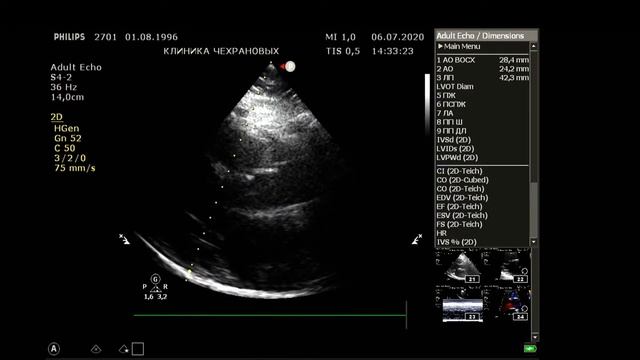

УЗИ БЦА - норма визуализация идеальная. Тот случай когда на обследование БЦА уходит 4 минуты без описания а описание минут 5-6. Для такой категории пациентов 20 минут на вполне достаточно. Но такой пациент скорее исключение из правил. УЗИ сердца - норма. На 12-й минуте - определение индексированного объема левого предсердия определение диастолической функции левого желудочка по тканевому допплеру.,